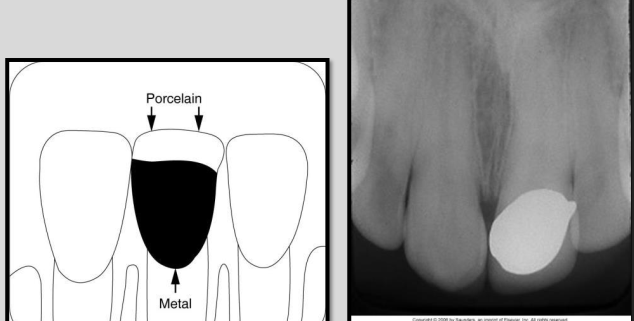

Describe Rampant caries.

Rampant caries refers to growing or spreading caries.

Advanced and severe affecting numerous teeth (can happen to both primary and permanent dentition)

Happens in children with poor dietary habits, nursing bottle syndrome or in adults with xerostomia (dry mouth) due to mediations.

Can also be a secondary condition to chemo radiation therapyÂ